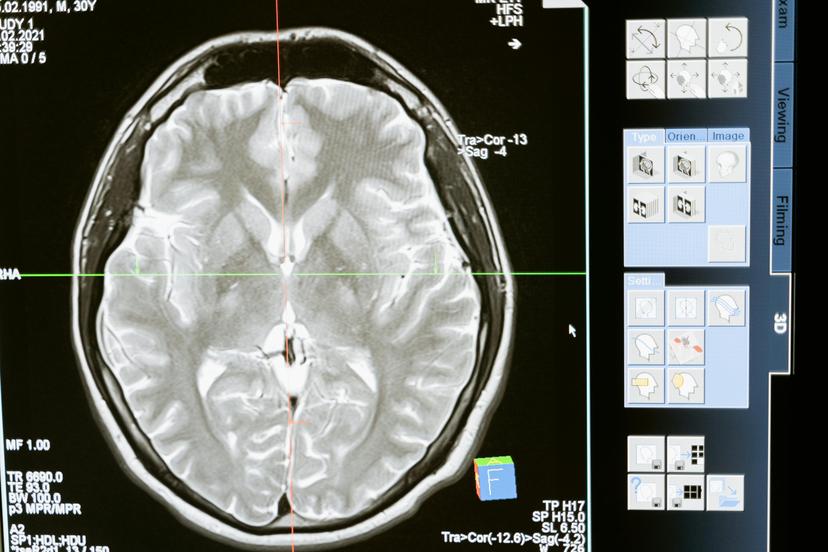

- Surveillez les signes d’anxiété ou de dépression: :L'anxiété et la dépression peuvent toucher jusqu'à 60 % des personnes atteintes de la maladie de Parkinson. La MP affecte certaines zones du cerveau qui stabilisent l'humeur, ce qui augmente le risque de dépression, en particulier lorsqu'elle est combinée à la qualité de vie des patients aux stades avancés de la maladie.